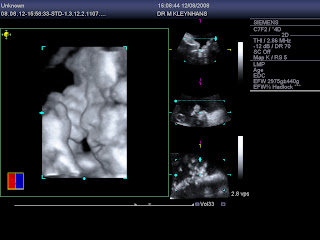

These are the 4D scans we had done when I was 36 weeks pregnant! Enjoy!

This is just a quick update. I finally managed to get my 4D scans, scanned, in order to post them on the blog. I had these scans done when i was 28 weeks pregnant and i am already 36 weeks. Time is really flying and I have 2 1/2 weeks to go before i meet my little boy. We are so excited.